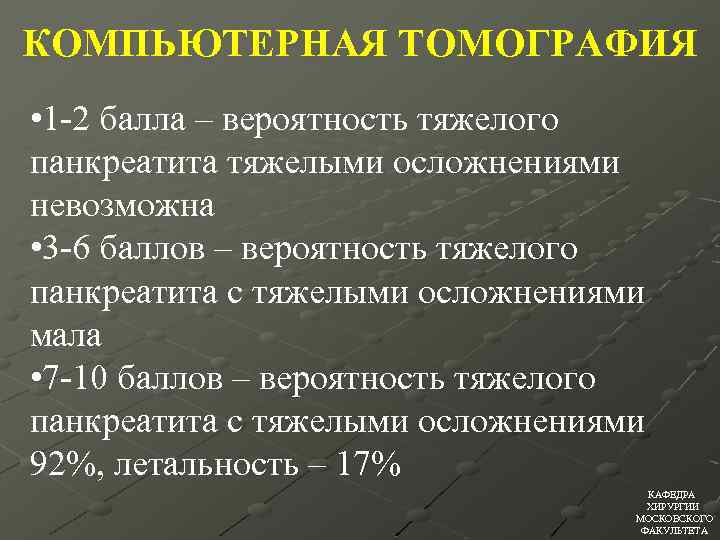

КОМПЬЮТЕРНАЯ ТОМОГРАФИЯ • А=0 • В=1 • С=2 • D=3 • Е=4 • Отсутствие некроза=0 • Некроз до 13 поджелудочной железы=2 • Некроз 50% поджелудочной железы=4 • Некроз >50% поджелудочной железы=6 КАФЕДРА ХИРУРГИИ МОСКОВСКОГО ФАКУЛЬТЕТА

КОМПЬЮТЕРНАЯ ТОМОГРАФИЯ • А=0 • В=1 • С=2 • D=3 • Е=4 • Отсутствие некроза=0 • Некроз до 13 поджелудочной железы=2 • Некроз 50% поджелудочной железы=4 • Некроз >50% поджелудочной железы=6 КАФЕДРА ХИРУРГИИ МОСКОВСКОГО ФАКУЛЬТЕТА

КОМПЬЮТЕРНАЯ ТОМОГРАФИЯ • 1 -2 балла – вероятность тяжелого панкреатита тяжелыми осложнениями невозможна • 3 -6 баллов – вероятность тяжелого панкреатита с тяжелыми осложнениями мала • 7 -10 баллов – вероятность тяжелого панкреатита с тяжелыми осложнениями 92%, летальность – 17% КАФЕДРА ХИРУРГИИ МОСКОВСКОГО ФАКУЛЬТЕТА

КОМПЬЮТЕРНАЯ ТОМОГРАФИЯ • 1 -2 балла – вероятность тяжелого панкреатита тяжелыми осложнениями невозможна • 3 -6 баллов – вероятность тяжелого панкреатита с тяжелыми осложнениями мала • 7 -10 баллов – вероятность тяжелого панкреатита с тяжелыми осложнениями 92%, летальность – 17% КАФЕДРА ХИРУРГИИ МОСКОВСКОГО ФАКУЛЬТЕТА